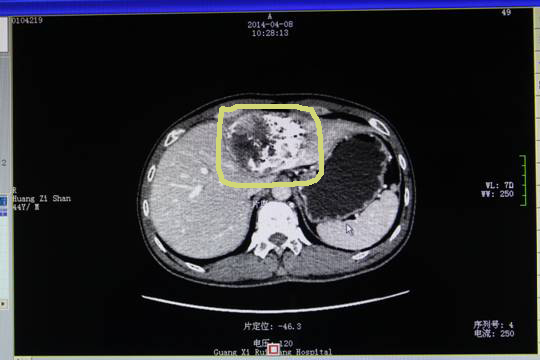

2014年3月6日黄先生开始做第一次栓塞,侯恩存主任解释:“肝动脉栓塞就是在腹股沟处切一个小口,通过一个导管在股动脉内进入肝脏,将供应肿瘤营养的血管堵塞,比较安全。”从第一次肝动脉栓塞后于4月8日复查的CT片(下图)上可以看到,白色部分为被成功栓塞的肿瘤。肿瘤轮廓内灰色的为未栓塞的肿瘤。

第一次栓塞后